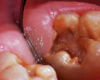

A 9-year-old boy had a partially erupted mandibular first molar with much hypocalcification of the occlusal surface and a large caries lesion involving the occlusal and buccal surfaces (Figure 1). The patient complained of continuing sensitivity to cold stimulus and air inspiration. Because the tooth was only partially erupted, consideration for stainless steel crown full coverage had to be delayed. As an interim repair, it was decided to debride the carious tooth substance and place a light-hardened calcium silicate/mineral trioxide aggregate (MTA) liner, followed by a bonded restoration. After inferior alveolar block anesthetic injection and cotton roll isolation, cavity outline form was cut using a high-speed, water-cooled, medium-grit cylindrical diamond bur (Figure 2). Insufficient eruption precluded use of a rubber dam. A large, round bur at slow speed was used to debride the carious enamel and dentin. The prepared surfaces were swabbed for two 60-second applications of a 5% glutaraldehyde/HEMA solution for desensitization and disinfection of the preparation.6,7 Cavity liner was then injected and spread over the deepest sections of the cavity floor and hardened with the visible light beam (Figure 3). After a self-etching bonding agent was applied over the remaining enamel surfaces, without the need for any type of matrix, an RMGI bioactive ionic resin-based composite was injected, in one portion, into the preparation and spread over the four cusps using a ball burnisher. This restorative complex was then photo-polymerized using two 20-second exposures of the visible light beam (1,200 mW/cm2). The restoration was trimmed and finished with large, round diamond burs at slow speed, and occlusion was evaluated with articulating paper and adjusted.

A 9-year-old presented with hypoplasia, hypocalcification, and caries.

Figure 1

The tooth was prepared for interim sedative restoration.

Figure 2